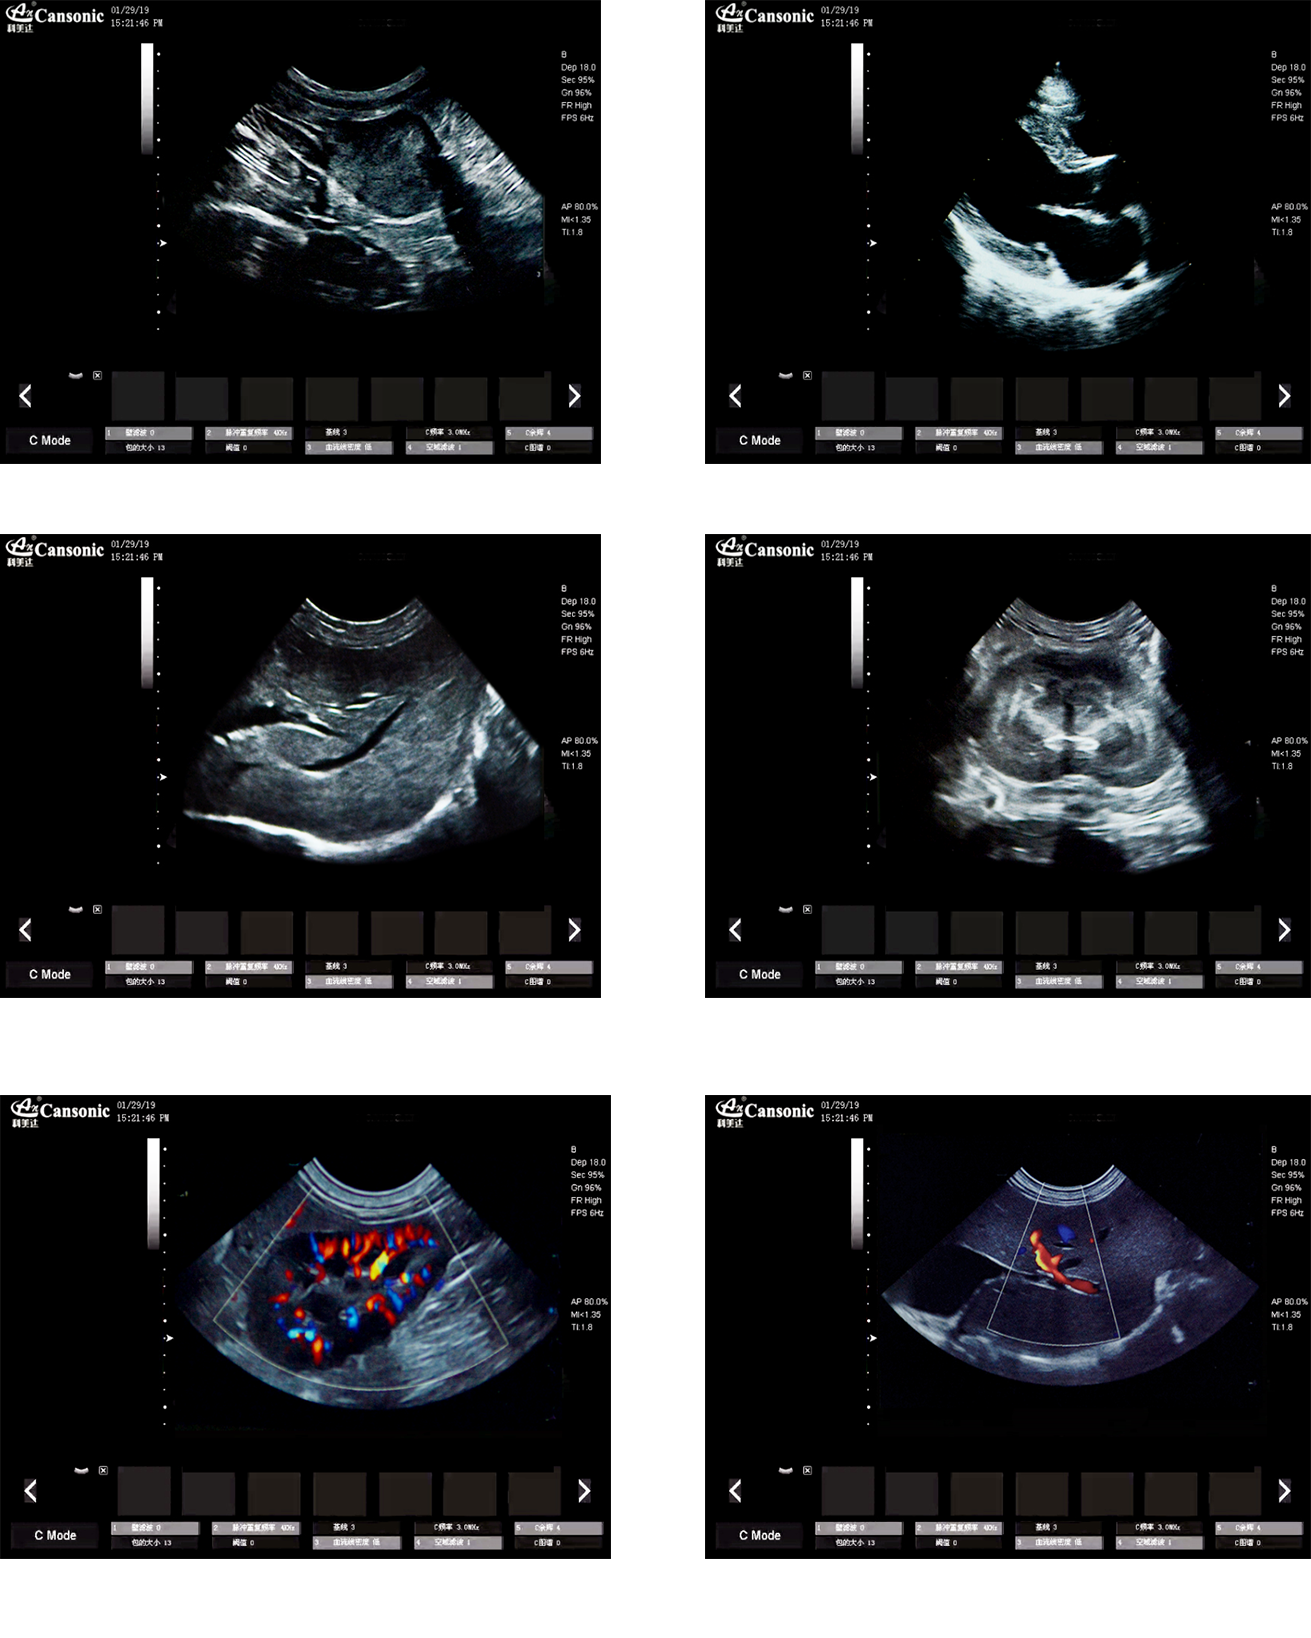

K10V

1、薈萃高端彩超的專業技術,各類型的專業獸用探頭,提供完整的動物臨床診療方案

2、專業的獸用彩超軟件,適合犬、貓、馬、牛、羊等各類大小動物彩超檢查

3、完備的獸用高端功能,能量多普勒POWER模式彩色多普勒Color成像模式

4、精準全數字濾波技術,有效降低多普勒噪聲及運動偽像,提升多普勒超聲圖像

臨床圖示